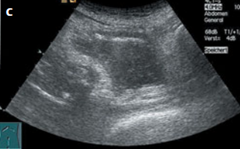

b Dilated, obstructed, anechoic renal pelvis. c Following bladder irrigation

(to clear blood clots causing bladder tamponade), ultrasound demonstrates

intravesical air (echogenic crescent along the bladder roof). Bright swirling echoes (blood) can be seen during irrigation